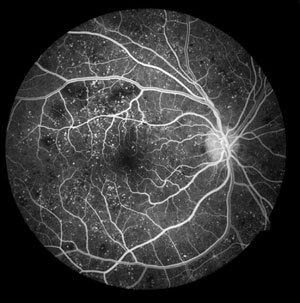

If the ophthalmologist Mr. Hatzinikolas observes diabetic retinopathy, he may request - advise you to undergo a special examination called fluorescein angiography or Optical Coherence Tomography (OCT) to determine whether and in which areas of the retina laser treatment is needed.

Fluorescein angiography (fluorescein angiography) is a test in which the dye fluorescein is injected into a vein in your arm, and the special fluid travels to the vessels of your eye within seconds. Photographs of the fundus of your eye are then taken with a special camera. These photographs reveal damage that is not visible with fundoscopy, such as areas of severely reduced oxygenation of the retina, as well as any signs of vascular leakage.